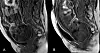

Franske forskere har tatt tredimensjonale bilder for å fange opp hvordan kraniet folder seg sammen under fødsel. (Foto: Ami et al.)

Nå har franske forskere tatt tredimensjonale bilder for å fange opp hvordan dette skjer. Ved hjelp at et MRI-apparat tok forskerne 3D-bilder av syv barns kranier og hjerner før fødselen, under utdrivningsfasen og som nyfødte.

Analysene av bildene avdekker at kraniet folder seg sammen hos alle de syv barna, ved at ulike deler av skallen overlapper hverandre i varierende grad.

Bildet viser hvordan hodeskalleplatene folder seg under fødsel. (Illustrasjon: Ami et al. )